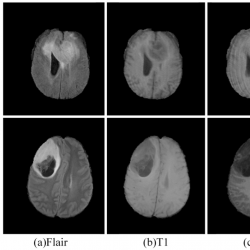

Three publicly available datasets were used for the experiments, namely BraTS 2019, BraTS 2020 and BraTS 2021 (Bakas et al., 2017; Menze et al., 2014; Baid et al., 2021). The BraTS 2019 dataset consists of 335 glioma patient cases for training and 125 samples of unknown tumour types for validation. The BraTS 2020 dataset training set consists of 369 glioma patient cases and the validation set consists of 125 cases of unknown tumour types. Due to the closure of the official validation process for BraTS 2021, we conducted a five-fold cross-validation using the BraTS 2021 training set, which includes 1251 glioma patient cases. Each sample in the dataset consists of four modalities: T1-weight (T1), post-contrast T1-weighted (T1ce), T2-weighted (T2), and T2 Fluid Attenuated Inversion Recovery (FLARE), as depicted in Fig. 5. The image size for each modality is $240\times 240\times 155$. Furthermore, the training set includes manually annotated ground truth labels by an expert, encompassing background (label 0), Non-Enhancing tumour (label 1), Peritumoural Edema (label 2), and Enhancing Tumour (label 4). To maintain the fairness of the experimental results, the validation set does not disclose the ground truth, and its segmentation results must be evaluated through an online server available at https://ipp.cbica.upenn.edu/. The MRI brain tumour segmentation objectives comprise three distinct regions: Enhancing Tumour (ET), Tumour Core (TC), and Whole Tumour (WT). Each tumour region corresponds to different labels: ET contains label 4, TC contains labels 1 and 4, and WT contains labels 1, 2, and 4.

infor574_g005.jpg

Fig. 5

MRI in different modes and ground truth.